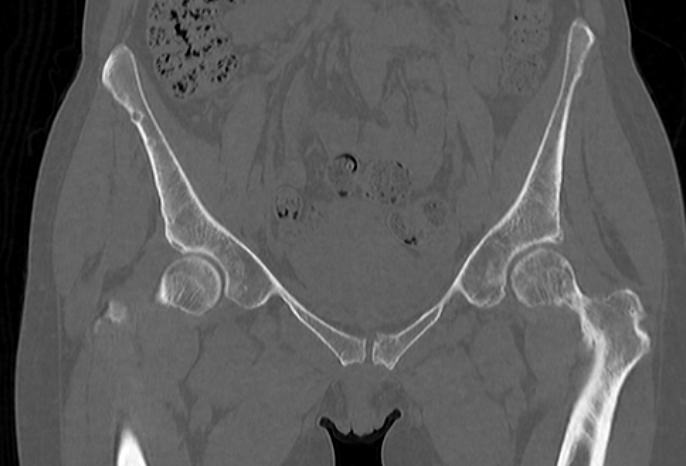

Для диагностики патологии костей таза применяются рентгенологические методы исследования, так как кости хорошо поглощают рентгеновские лучи и поэтому ярко видны на снимках. Современным наиболее информативным способом оценки состояния костных структур таза является мультиспиральная компьютерная томография. По сравнению с обычным рентгеном, когда изображения костей на снимках получается только в одной плоскости и накладывается друг на друга, мультиспиральная КТ позволяет получать послойные изображения в различных плоскостях. Томограф производит множество тончайших срезов исследуемой зоны толщиной от 0,5 мм, которые затем трансформируются при помощи компьютерной обработки данных в трехмерные пространственные модели.

Методика мультиспиральной КТ используется для диагностики переломов костей таза, когда обычный рентген недостаточно информативен. На снимках и трехмерных изображениях хорошо видны фрагменты костных отломков и взаимное расположение костей таза. КТ также назначается перед операцией и после хирургического вмешательства для оценки успешности проведенной операции и для контроля процессов регенерации костной ткани.